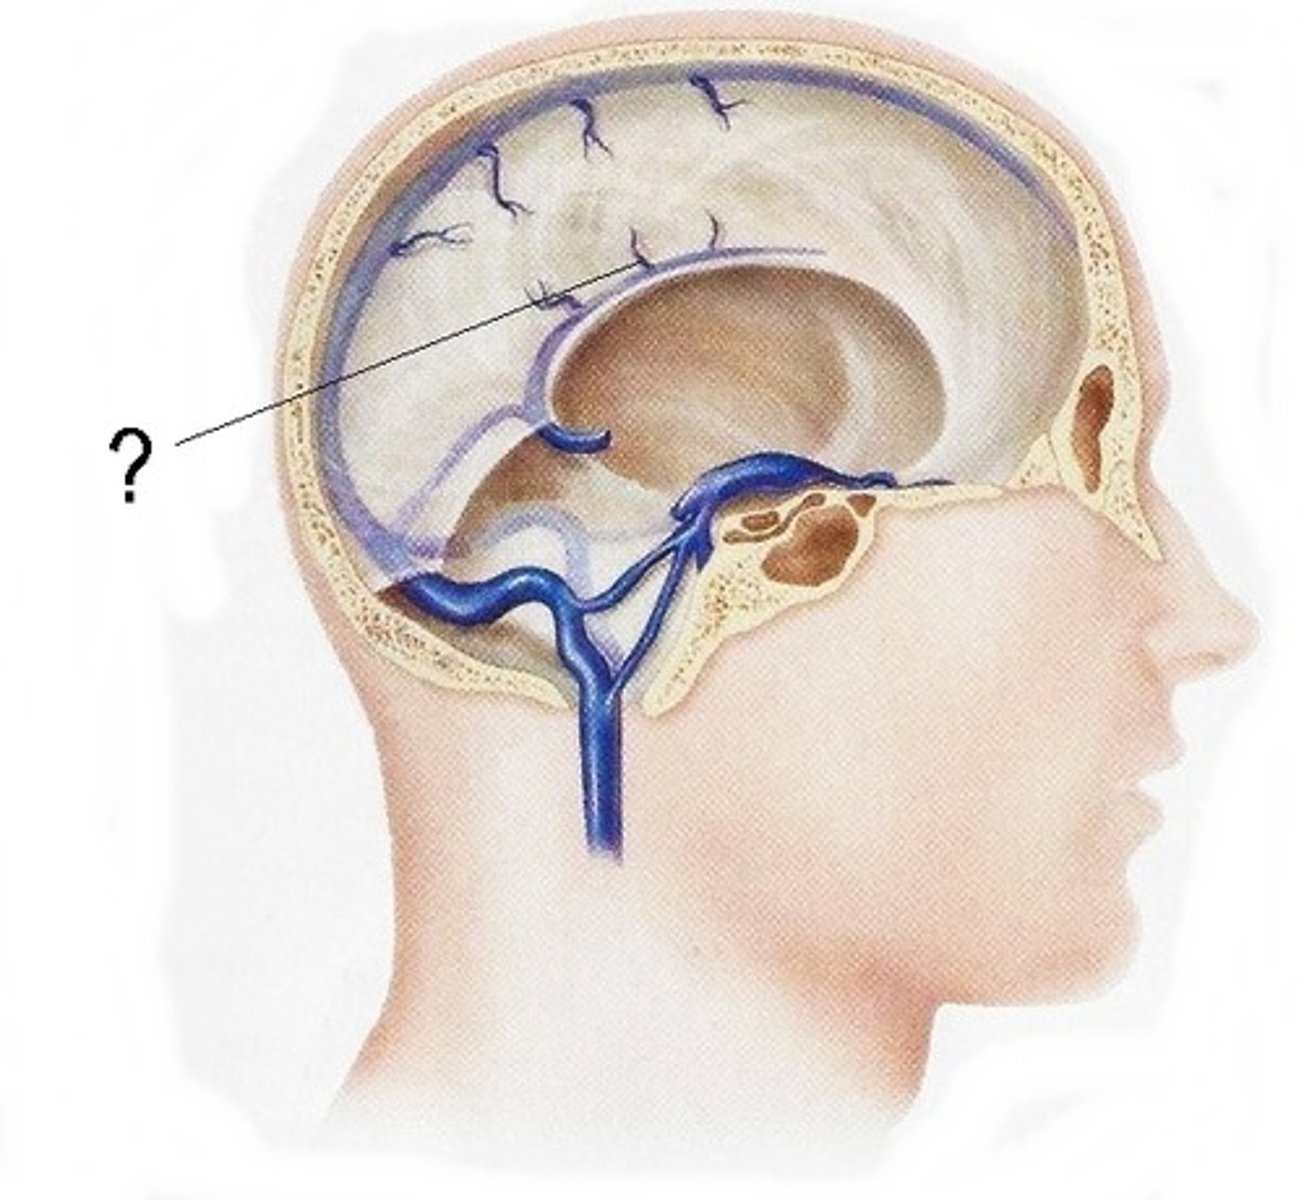

what are dural folds?

folded layers of dura where there is no sinus

falx cerebri

separates the two cerebral hemispheres

tentorium cerebelli

separates cerebrum from cerebellum

falx cerebelli

separates the two hemispheres of the cerebellum